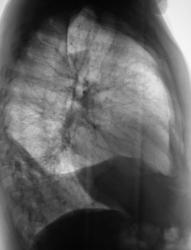

Пациент был направлен в рентгеновский кабинет терапевтом с диагнозом "Правостороняя пневмония". Было произведено стандартное исследование.

Было назначено противовоспалительное лечение. Через 1 неделю проведен "рентген-контроль".

правостороннего плеврального выпота в проекции средней доли.

Согласен с коллегой, но по-моему, кроме это выпот есть и заднем синусе. Картина в серия снимков №7-9, с небольшой положительной динамикой в сравнении данными в серии №4-6.

Кажущееся затемнение в области средней доли симулирует суперпозиция приподнятого правого купола диафрагмы и тени сердца. В заднем синусе справа - небольшой выпот, а со стороны диафрагмы, кроме элевации и выпрямления, присутствует картина диафрагматита в задних отделах. Вероятно необходимо ультразвуковое исследование органов брюшной полости и забрюшинного пространства для поиска первопричины данного состояния там. Динамика процесса за время наблюдения - явно положительная.